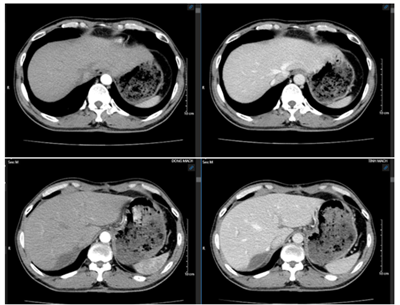

Ca lâm sàng: Điều trị đích bệnh nhân ung thư phổi không tế bào nhỏ giai đoạn muộn di căn nhiều cơ quan, tại Trung tâm Y học hạt nhân và Ung bướu – Bệnh viện Bạch Mai

Ung thư phổi là nguyên nhân hàng đầu gây tử vong do ung thư trên toàn thế giới. Trong đó, ung thư phổi không tế bào nhỏ (NSCLC) là thể thường gặp nhất, chiếm khoảng 85% các trường hợp [1]. Phần lớn bệnh nhân được chẩn đoán ở giai đoạn tiến...